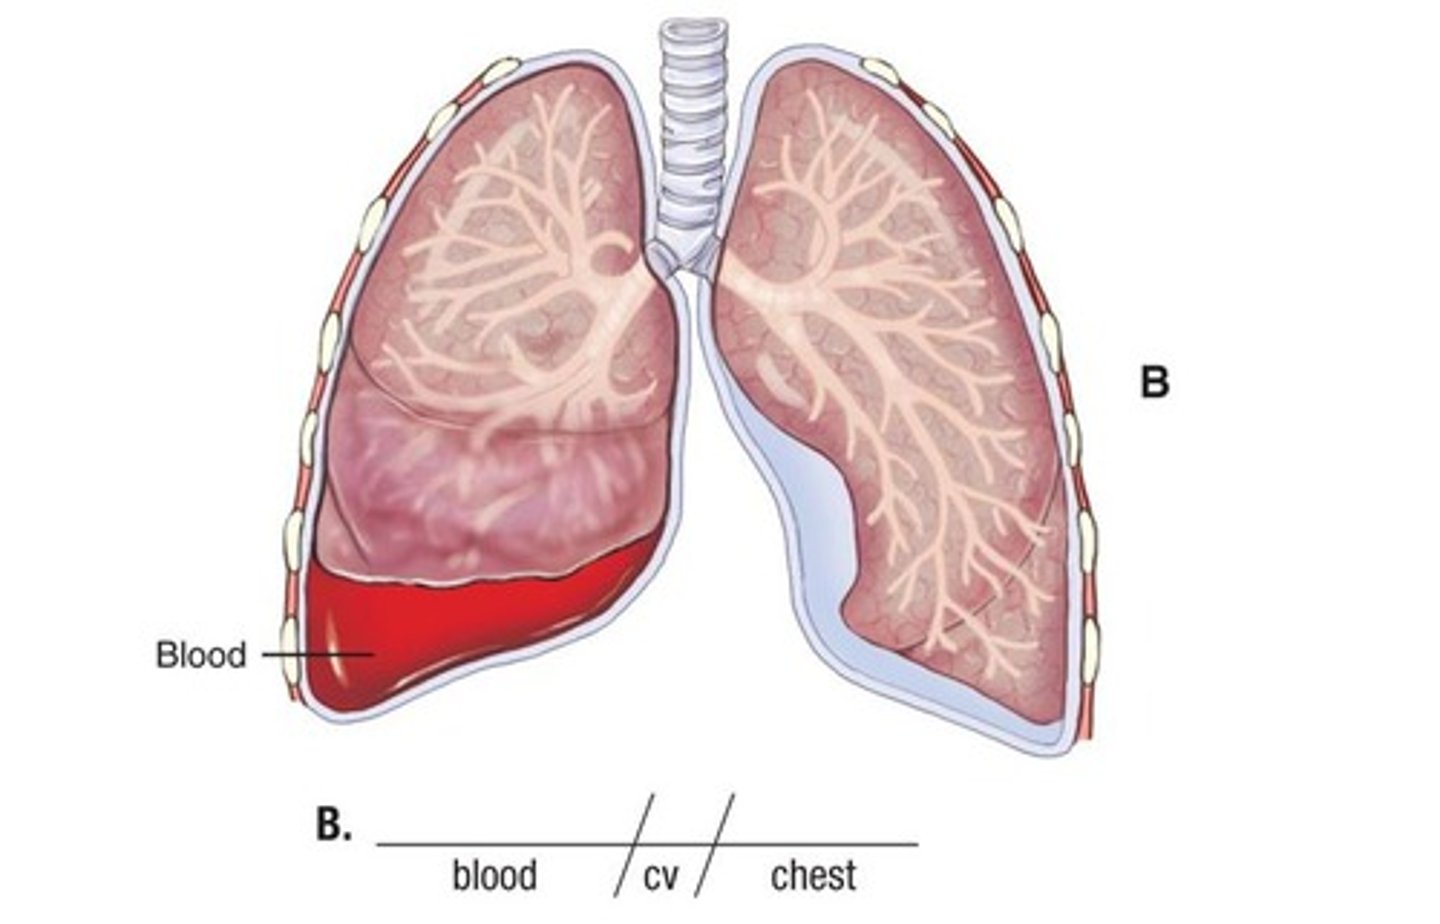

hemothorax

blood in the chest cavity (pleural space)